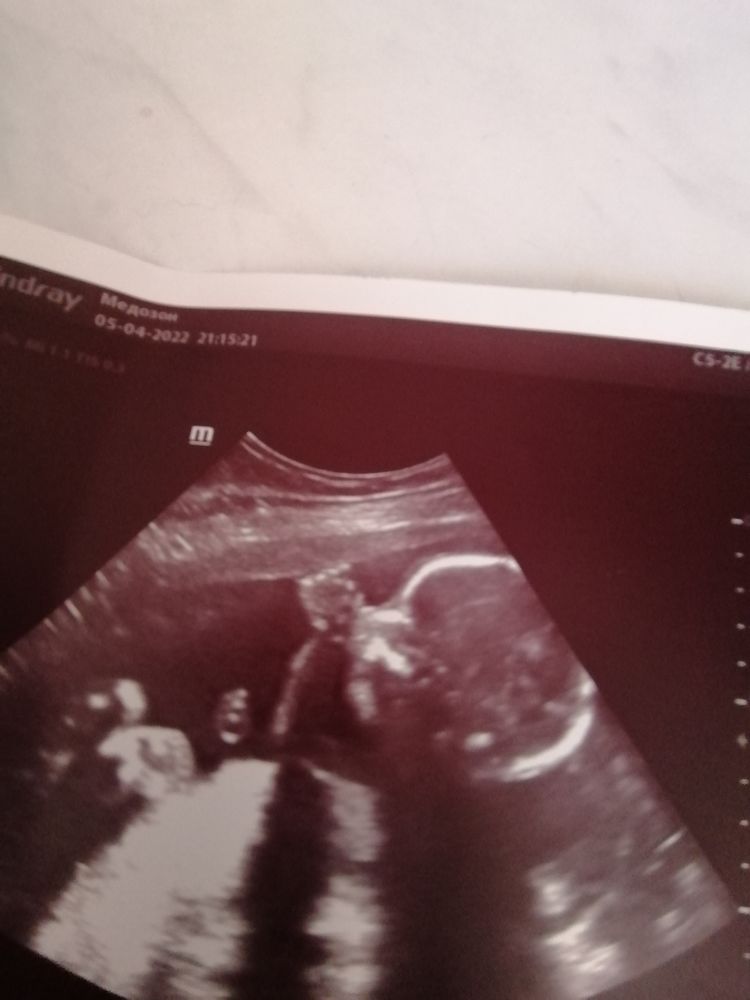

Прошли 2 скрининг и точно узнали пол малыша 💥💯

классно как)) нам 19 неделек...и весим 305 гр... На втором скрининге только измерения? Идем 11ого на второй скрининг)

Наши 20 неделек Животик на 26 недели